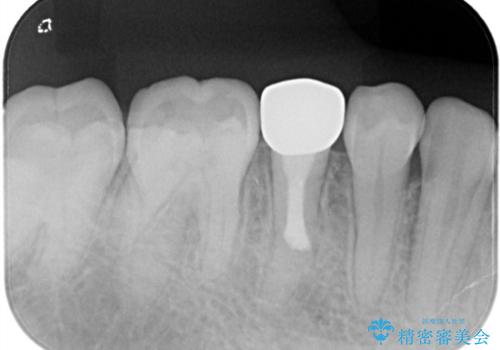

【根管治療】噛んだ時にしみる。最近になってズキズキ痛み、長引く痛みがある

担当医 河口智英